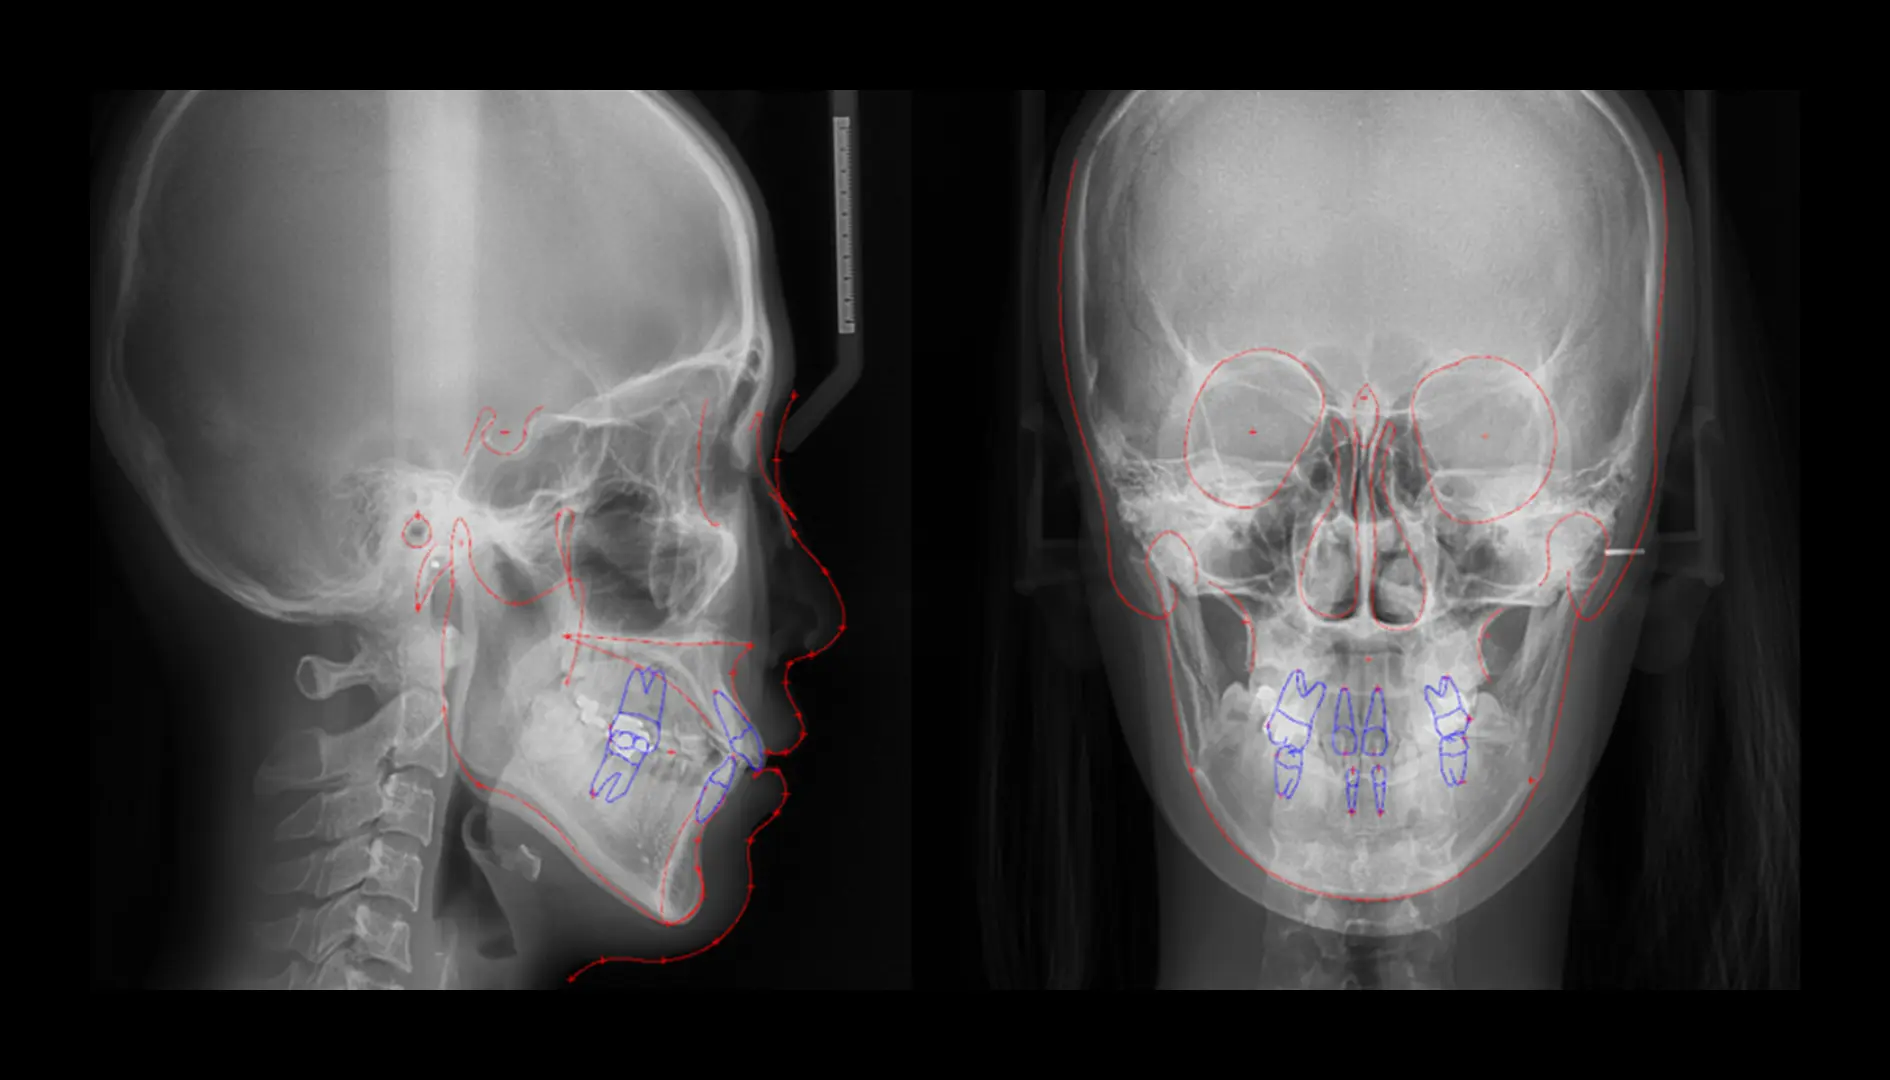

오토 트레이싱환자의 X-ray (측면 & 정면)에서의 디지털 트레이싱

클릭 한번으로 빠르고 정확한 AI기반의 자동 트레이싱